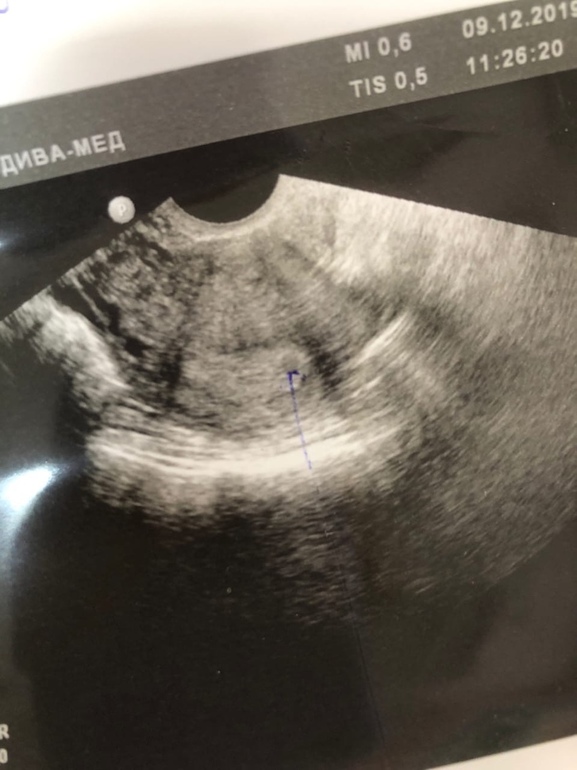

УЗИ, КТГ, доплерВсем привет) Принимайте в свои ряды) Сегодня - завтра день предполагаемых месячных, тесты полосатые. Пошла сегодня на прием к платному врачу и она сделала мне узи чтобы убедиться что беременность маточная. Срок маленький и толком ничего не видно, нашла что-то похожее на яичко, и кисту (ЖТ под вопросом), сказала что задержку может давать эта киста, но ХГЧ говорит об обратном. Сдавала кровь в динамике, гормон растет)

Стрелочкой выделен вроде как малышик)